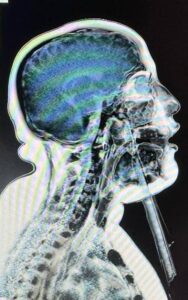

نجح فريق طبي بقسم جراحة الوجه والفكين والجمجمة بمستشفى العجوزة التخصصي في تحقيق إنجاز طبي جديد، حيث تم التعامل مع حالة نادرة ومعقدة لطفل يبلغ من العمر 15 عامًا تعرض لسقوط أدى إلى دخول جسم غريب بطول 20 سم اخترق الرقبة واللسان وسقف الحلق وتوقف أمام قاع العين مباشرة ممتدًا حتى الجمجمة.

وقد تسبب هذا الاختراق في تهتك شديد بالأنسجة والأوردة والشرايين، كما شكل تحديًا كبيرًا لفريق التخدير نظرًا لتمركز الجسم الغريب أمام مجرى التنفس وصعوبة التعامل معه أثناء التخدير.

ورغم دقة الحالة وخطورتها، نجح فريق جراحة الوجه والفكين بالمستشفى في استخراج الجسم الغريب بدقة عالية وتقطيب الجروح والقطوع الجراحية، دون الحاجة إلى إجراء شق حنجري كما كان مقررًا، كما خرج المريض من غرفة العمليات إلى غرفته مباشرة بحالة مستقرة دون الحاجة إلى الدخول للرعاية المركزة أو استخدام أجهزة التنفس الصناعي.